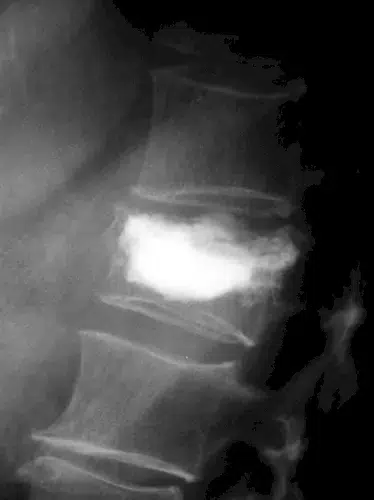

| ▸ | Röntgen Erkennung von Knochenbrüchen (zuverlässige Ergebnisse erst im späteren Krankheitsverlauf – neue, starke Rückenschmerzen; chronische Rückenschmerzen unbekannter Ursache; hohes Lebensalter; niedrige Knochendichte; mehrere, alte Brüche; Größenverlust von > 5 cm seit 25. Lebensjahr und > 2 cm bei Kontrolluntersuchungen) |

Röntgenaufnahmen von verschiedenen Knochenbrüchen bei Osteoporose

Diese Diagnostikmethoden kombiniert sind von großer Bedeutung, um individuelle Risikoprofile zu erstellen und eine präzise Behandlung einzuleiten. Eine frühzeitige Untersuchung ermöglicht es Ihnen, gezielt Maßnahmen zu ergreifen und so die Stabilität Ihres Knochengerüsts langfristig zu sichern.